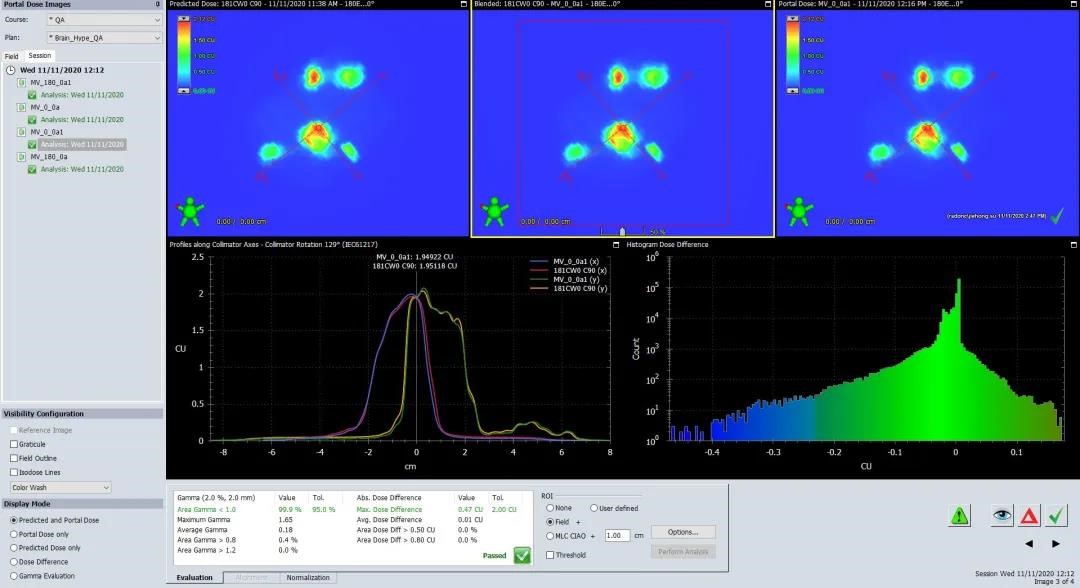

4、剂量验证

Potal Dosimetry剂量验证